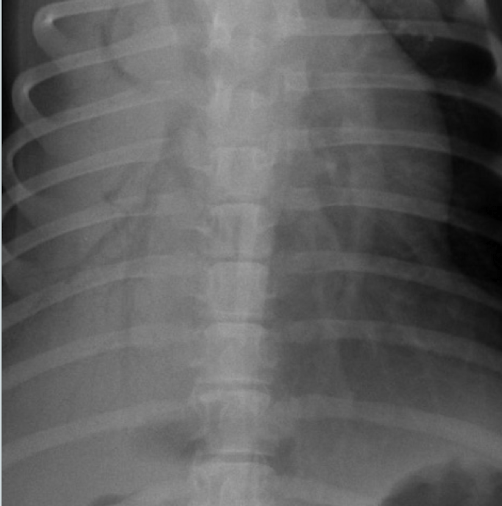

Harry is a 7yo Boxer who underwent surgery for a gastric foreign body. He had a difficult anesthetic recovery and his ET tube contained fluid when he was extubated. The following day he he is febrile, depressed, tachypnea and dyspnea.

What lung pattern?

ddx?

Alveolar Pattern (note air bronchograms and border effacement of the silhouette)

ddx: bronchopneumonia secondary to aspiration post surgically